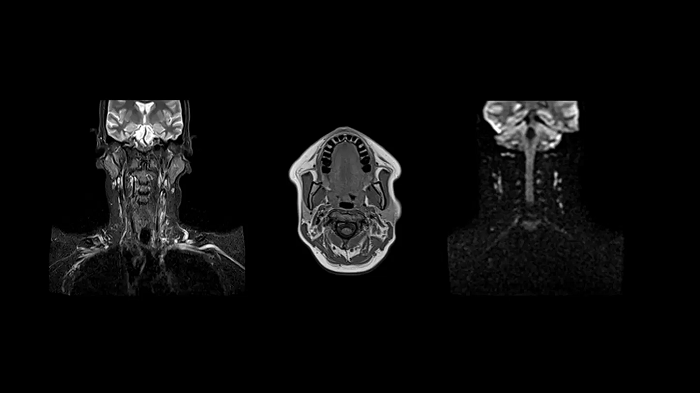

Neck

Excellent soft tissue contrast in the neck

All-inclusive soft tissue examination of the head with outstanding image quality for T1, T2, and diffusion contrast.

- Head/Neck Coil

- Spine Coil

Image Courtesy: University Hospital Erlangen, Germany | Image-ID: 4aaaa0458

Spine

C-Spine - T2 TSE

Integrate Head/Neck and Spine Coil to gain outstanding C-Spine images with T2 TSE.

- Head/Neck Coil

- Spine Coil

Image Courtesy: University Hospital Erlangen, Germany | Image-ID: 4aaaa0440